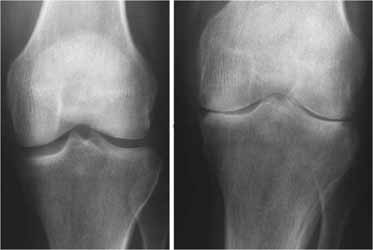

جی پلاس، دکتر خسرو شایان در خصوص عوامل ابتلا به بیماری رماتیسم، اظهار کرد: رماتیسم بیماری است که مربوط به واکنش ایمنی بدن بوده و عوامل ابتلا به آن داخلی هستند. وی با اعلام اینکه برای این بیماری پیشگیری خاصی نداریم، عنوان کرد: به این دلیل که بیماری رماتیسم مربوط به اعضای داخلی بدن و اختلالات آن‌ها است، نمی‌توانیم پیشگیری خاصی را برای آن داشته باشیم. شایان با اشاره به علائم ابتلا به این بیماری، تصریح کرد: زمانی که افراد با تورم و خشکی مفاصل از خواب برمی‌خیزند از علائم ابتلا به بیماری رماتیسم است. معمولا افرادی که رماتیسم مفصلی دارند دچار کم‌خونی شده و بسیار ضعیف هستند. این متخصص ارتوپدی، جراحی استخوان و مفاصل با بیان اینکه افراد در سنین پایین‌ نیز به این بیماری مبتلا می‌شوند، گفت: در بیشتر موارد افراد در سنین نوجوانی و جوانی به رماتیسم مفصلی مبتلا می‌شوند، اما در سنین بالاتر مانند اوایل میانسالی نیز علائم این بیماری خود را نشان می‌دهد. وی به درمان‌های این بیماری اشاره و خاطرنشان کرد: تقویت عضلات مفصلی که به رماتیسم مبتلا شده، جلوگیری از وارد کردن فشار، استفاده از داروهای خاص و ... پیشرفت این بیماری را کندتر می‌کند. شایان ادامه داد: بیماری رماتیسم با آزمایش‌های رماتیسمی و رادیوگرافی مشخص می‌شود. منبع: ایسنا